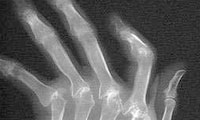

در پوکی استخوان، استخوان ضعیف شده و با کوچک ترین ضربه دچار شکستگی می شود. این پدیده در سنین سالمندی شایع است، اما با اقدامات ساده یی می توان آن را به تأخیر انداخت یا شدت آن را کاهش داد.

اهمیت پوکی استخوان در آن است که اغلب تا زمان شکستگی استخوانی علامتی ندارد! ستون فقرات، استخوان ران، لگن، مچ دست و انتهای ساعد به ترتیب شایع ترین محل هایی هستند که در اثر پوکی استخوان دچار شکستگی می شوند. بسیاری از شکستگی های ستون فقرات تنها با درد شدید پشت همراه هستند و علامت دیگری ندارند. هم چنین انحراف ستون مهره ها در اثر جوش خوردن خود به خودی آن ها می تواند از علایم این بیماری باشد.

پوکی استخوان چگونه منجر به شکستگی می شود؟

حدود پنج درصد استخوان هایی که استحکام کافی برای حفظ تعادل بدن نداشته باشند به راحتی متعاقب نیروهای جزیی مانند زمین خوردن یا سقوط از پله دچار شکستگی می شوند، به همین دلیل شایع ترین علت شکستگی های ناشی از پوکی استخوان سقوط و زمین خوردن است. عواملی مانند موانع محیطی، نورکم، اختلالات بینایی، فراموشی و استفاده از داروهای خواب آور در افزایش احتمال سقوط و شکستگی نقش دارند.